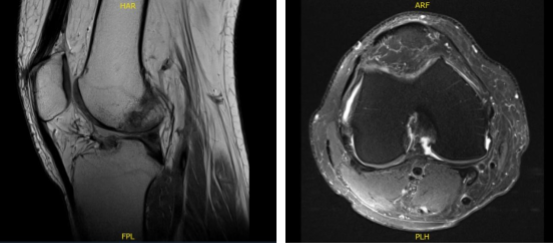

MRI presented and reviewed by the doctor. It showed that the left knee of the patient is intact in medial and lateral meniscus and has no acute osseous injury but has small joint effusion. The central trochlea has a focal chondral fissure and fibrillation in the midportion of the medial femoral condyle.

However, the right knee of the patient, prior partial lateral meniscectomy with diminutive anterior horn with a re-tear in the body of the lateral meniscus. Because of the extrusion of the body the lateral meniscus causes too mild to moderate tricompartmental osteoarthritis with small joint effusion.

The left knee x-ray that completes with patella shows that there are no acute fractures and significant degenerative changes while the right knee has no fractures but have mild osteoarthritic degenerative changes.